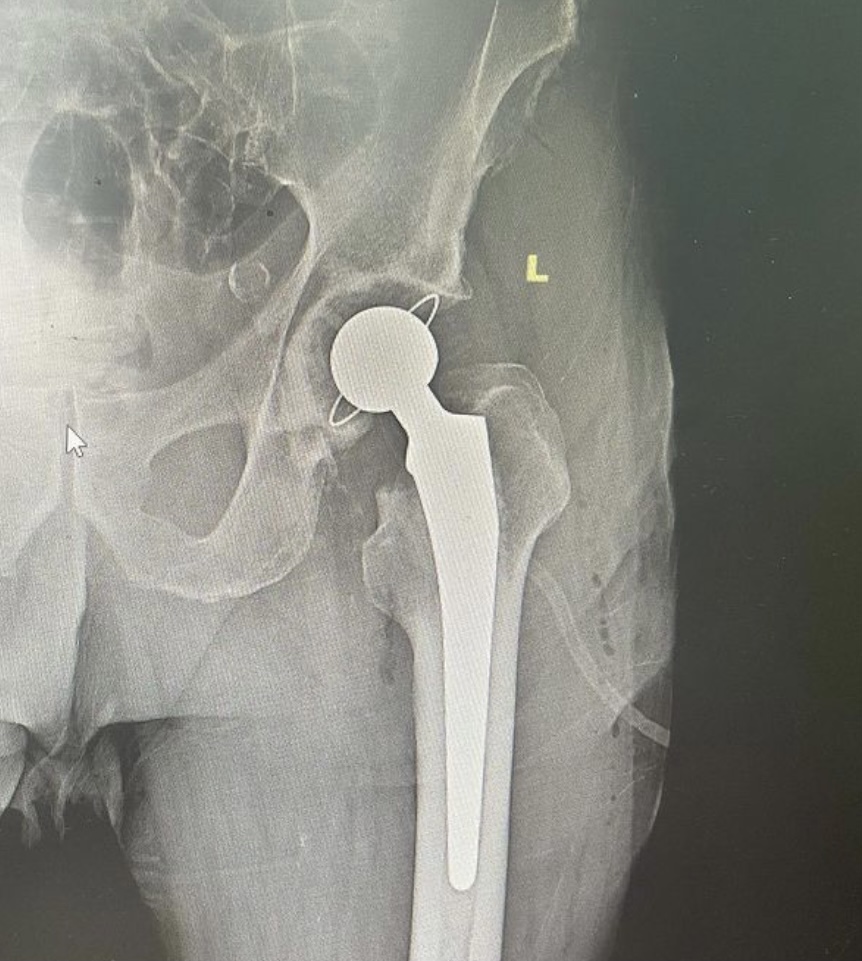

Представляем два рентгенснимка: в первом случае – 50-летний пациент с субкапитальным переломом шейки бедренной кости. Выполнено тотальное эндопротезирование тазобедренного сустава эндопротезом бесцементной фиксации.